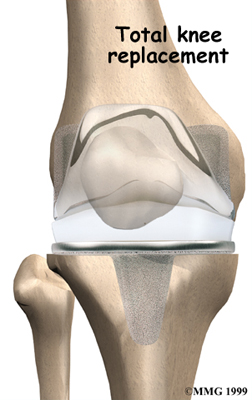

Artificial Knee Replacement

An artificial knee replacement is the ultimate solution for advanced knee OA.

Surgeons prefer not to put a new knee joint in patients younger than 60. This is because younger patients are generally more active and might put too much stress on the joint, causing it to loosen or even crack. A revision surgery to replace a damaged prosthesis is harder to do, has more possible complications, and is usually less successful than a first-time joint replacement surgery.

Related Document: FYZICAL Buffalo's Guide to Artificial Joint Replacement of the Knee